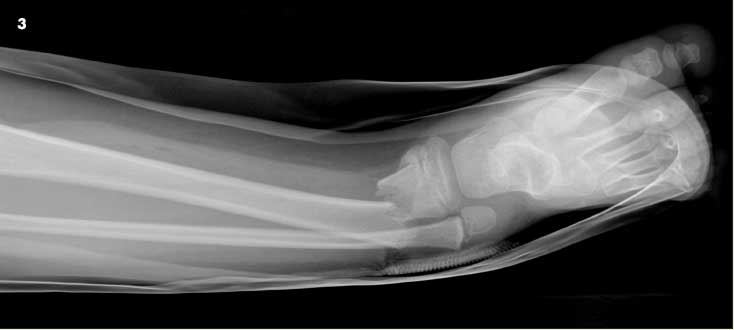

A 6-year-old boy was a passenger on an adult-sized ATV with his uncle. The ATV rolled over on both of them when the uncle lost control. The boy was wearing a chest protector at the time but no helmet. He sustained extensive injuries to both inguinal areas and to his mid-anterior thighs and lower legs. Figure 3 shows an angulated, displaced distal tibia as well as fibula fractures. CT scans and an anteroposterior radiograph of the pelvis (Figure 4) revealed bilateral nondisplaced pelvic bone fractures involving the right superior pubic ramus and bilateral inferior pubic rami. The open right tibia wound was extended surgically, irrigated copiously, and the fracture was reduced. Intravenous antibiotic therapy was administered for 48 hours. A drain was placed in the open wound, and the patient was placed in a long leg cast (Figure 5). The drain was removed in 2 days through an opening in the cast. The patient healed without complications.